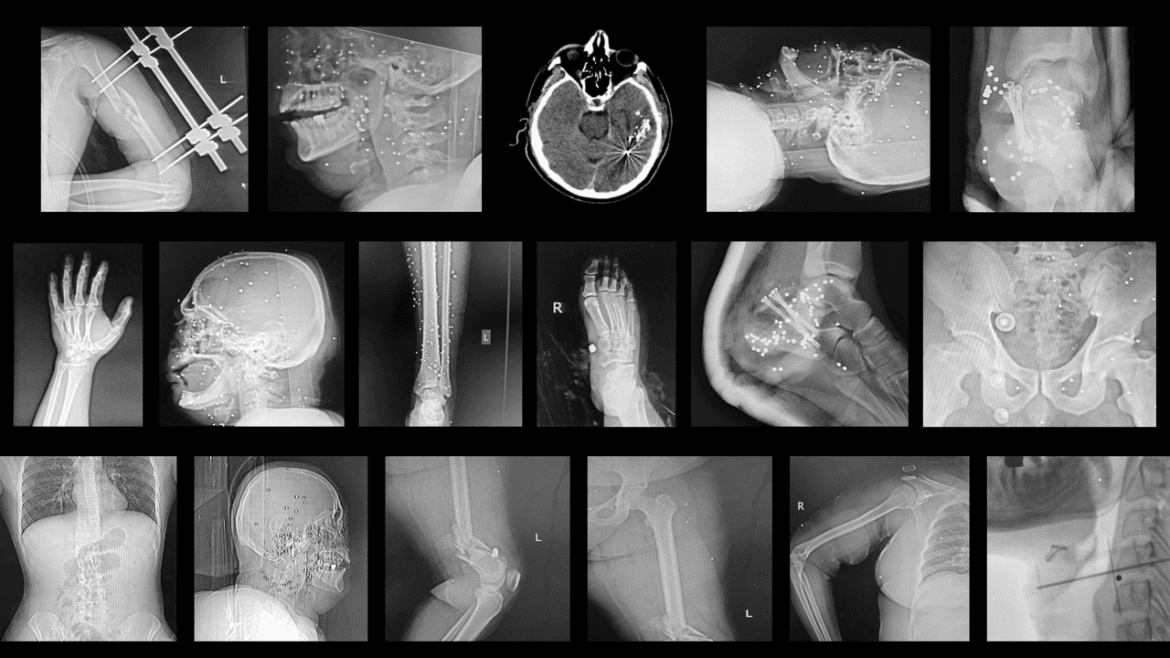

Medical workers have begun quietly doing their own record-keeping. One hospital employee in the northern city of Rasht told me that he had photographed hundreds of pieces of evidence, including CT scans and X-rays, from two emergency wards where he had volunteered during the massacre. “I want the world to know that these people existed, and that they have paid a price for their freedom,” the employee, who I will call Anush, told me. So far, he has collected records for nearly five hundred admitted patients, the majority of whom suffered trauma injuries. The images and scans, which he shared with me, compose an eerie tableau of the dystopian scenes that he witnessed in January: one X-ray showed a bullet that shattered the femur of a forty-seven-year-old mother, who had tried to shield her son from gunfire. One brain scan showed a metal pellet, which had partially blinded a nurse after she was shot in the head while exiting the hospital. “The wards felt like a war zone, run by regime thugs,” Anush said. Agents in plain clothes followed protesters into operating rooms, then detained them when they had completed their medical treatment. On several occasions, Anush said that he saw officers intervene during a surgical procedure, resulting in scuffles with medical staff. A medical intern was hospitalized after he was shot with metal pellets at close range.